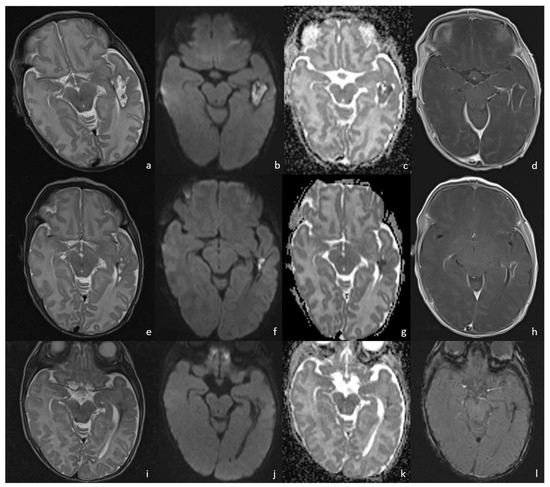

5.1. Choroid Plexitis and Ventriculitis

- Early cerebritis stage (3–5 days): Bacteria infiltrate the vessels causing vessel wall inflammation and vessel necrosis, which lead to blood barrier disruption and parenchymal invasion. The resulting cerebral infection, namely the early cerebritis, is limited to a focal portion of the brain, does not present a capsule, and presents a coexisting edema. In MRI, early cerebritis is seen as an inhomogeneous and ill-defined area of hyperintensity on T2WI and hypointensity on T1WI, surrounded by edema appearing hypointense on T1WI and hyperintense on T2WI. It presents a diffusion restriction on DWI/ADC in relation to cytotoxic edema and inflammatory hypercellularity. Hemorrhagic foci present as T1WI hyperintense areas within the lesion. After contrast administration, a patchy enhancement is observed, yet no capsule may be identified. On the US, early cerebritis appears as an ill-defined area of inhomogeneous echogenicity presenting increased vascularity on Transcranial Doppler, pairing CT findings, with an ill-defined area of inhomogeneous hypodensity with inhomogeneous and patchy enhancement.

- Late cerebritis (5–14 days): Cerebritis progressively evolves to show a necrotic core and an initial encapsulation. This stage flows into and partly overlaps with the early capsule stage since this last represents a progression with similar, yet more advanced features of the late cerebritis stage. In MRI, the late cerebritis results in a focal formation characterized by a necrotic core, appearing inhomogeneous on both T1 and T2WI, without a complete and regular contrast peripheral enhancement, yet with a defined diffusion restriction on DWI/ADC. On the US, the appearance is similar to the early cerebritis, yet the lesion appears more focal and the core starts becoming hypoechogenic, similar to CT showing a significantly hypodense core in the lesion with irregular and incomplete peripheral enhancement. Early capsule formation (14–30 days): The cerebritis is becoming an abscess since the capsule is evident, yet it is incomplete and thin and appears as a hyperintense rim on T1WI and a hypointense rim on T2WI with contrast enhancement on T1WI.

- Early capsule formation (2 weeks to 2 months): the lesion presents diffusion restriction on DWI/ADC, mainly in relation to hypercellularity. Sonographically, the lesion presents a well-defined hypoechoic core and an incomplete hyperechoic rim. CT shows a well-defined hypodense core and an incomplete peripheral enhancement.

- Late capsule formation (weeks to months): The parenchymal abscess presents a necrotic core, appearing hypointense on T1WI and hyperintense on T2WI with diffusion restriction on DWI/ADC. The capsule is inhomogeneously thick, appearing thicker towards the cortex and thinner towards the ventricles, appears isointense on T1WI and hypointense on T2WI, and presents an intense enhancement. On the US, the abscess presents a well-defined hypoechoic core and a complete hyperechoic rim, pairing CT that shows a well-defined hypodense core and a complete peripheral enhancement.